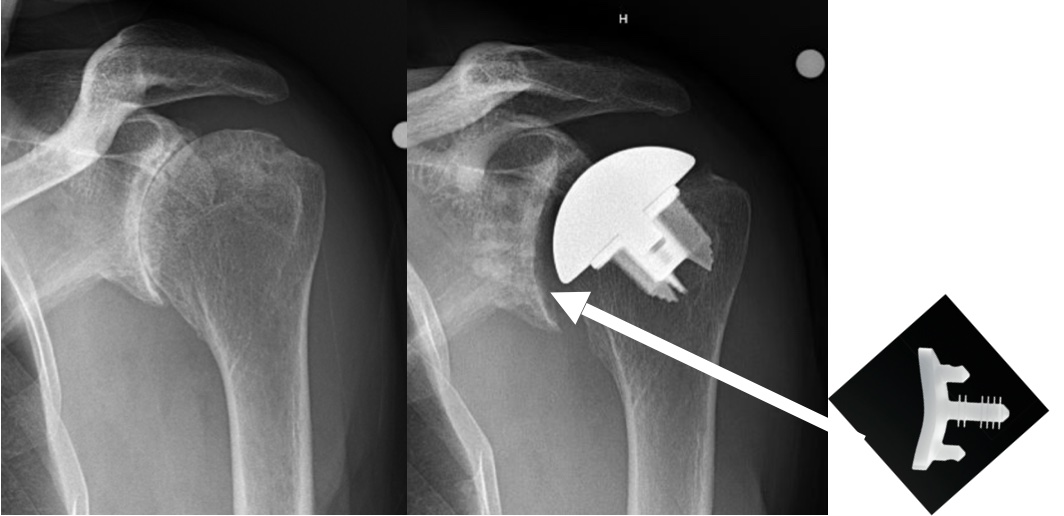

Anatomic total shoulder replacement requires a good rotator cuff. The replacement glenoid is made of plastic (ultra high molecular weight polyethylene). While most severely arthritic shoulders require glenoid replacement, there are occasional cases that can be treated with a humeral head resurfacing or a humeral head replacement can be performed. The ream and run procedure with a humeral head replacement and smoothing of the glenoid is an option for physically active, often younger patients, who want to participate in heavy physical activities and avoid the potential problems associated with anatomic glenoid replacement. The are some patients with osteoarthritis who have severe glenoid bone deformities and/or rotator cuff tearing who are treated with a reverse total shoulder. Reverse total shoulder was developed for the treatment of shoulder with severe rotator cuff tears. More recently, use of reverse total shoulder has expanded to some osteoarthritic shoulders. This is currently considered an off-label use of reverse total shoulder.

A reverse total shoulder replacement is specifically designed to be used in cases that do not have a functioning rotator cuff. The implants include a metal hemisphere that is attached to the glenoid/scapula and a metal humeral implant that has a plastic (polyethylene) socket.